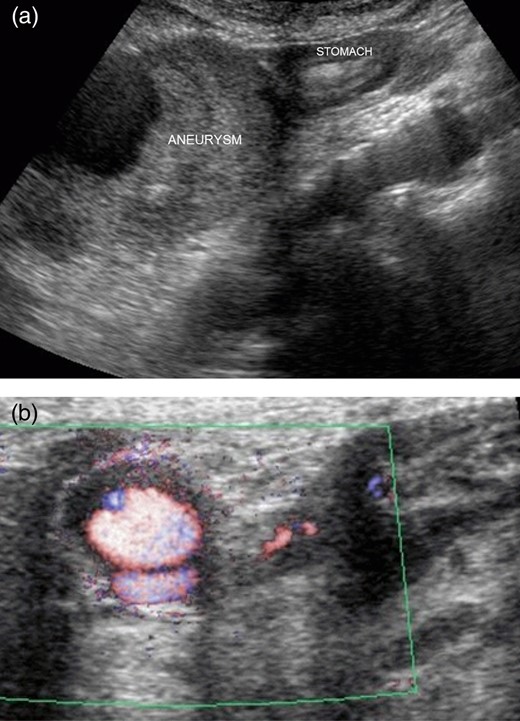

An 85-year-old man complaining of vague abdominal discomfort was admitted to our hospital. He had a medical history of arterial hypertension. Upon admission, his general status was stable. A pulsatile 8 × 7-cm mass in the right upper abdomen was noticed on clinical examination. Abdominal arterial aneurysm was diagnosed, and imaging studies were performed. Abdominal ultrasonography showed that the mass was present on the border of the greater curvature of the stomach, and blood flow was observed inside it (Fig. 1a and b). The mass was not connected to the abdominal artery. Computed tomography of the abdomen showed a huge arterial aneurysm in the right gastroepiploic artery, and the left gastroepiploic artery was meandering and expanding (Fig. 2a and b). There was no bleeding or ascites in abdominal cavity. Accordingly, an image diagnosis of GEAA was made. Because of the huge size of the aneurysm and the predicted high risk of perforation, surgical intervention was planned.

(a) Abdominal ultrasonography showed that the mass was present on the border of the greater curvature of the stomach. (b) Blood flow was observed inside the mass.